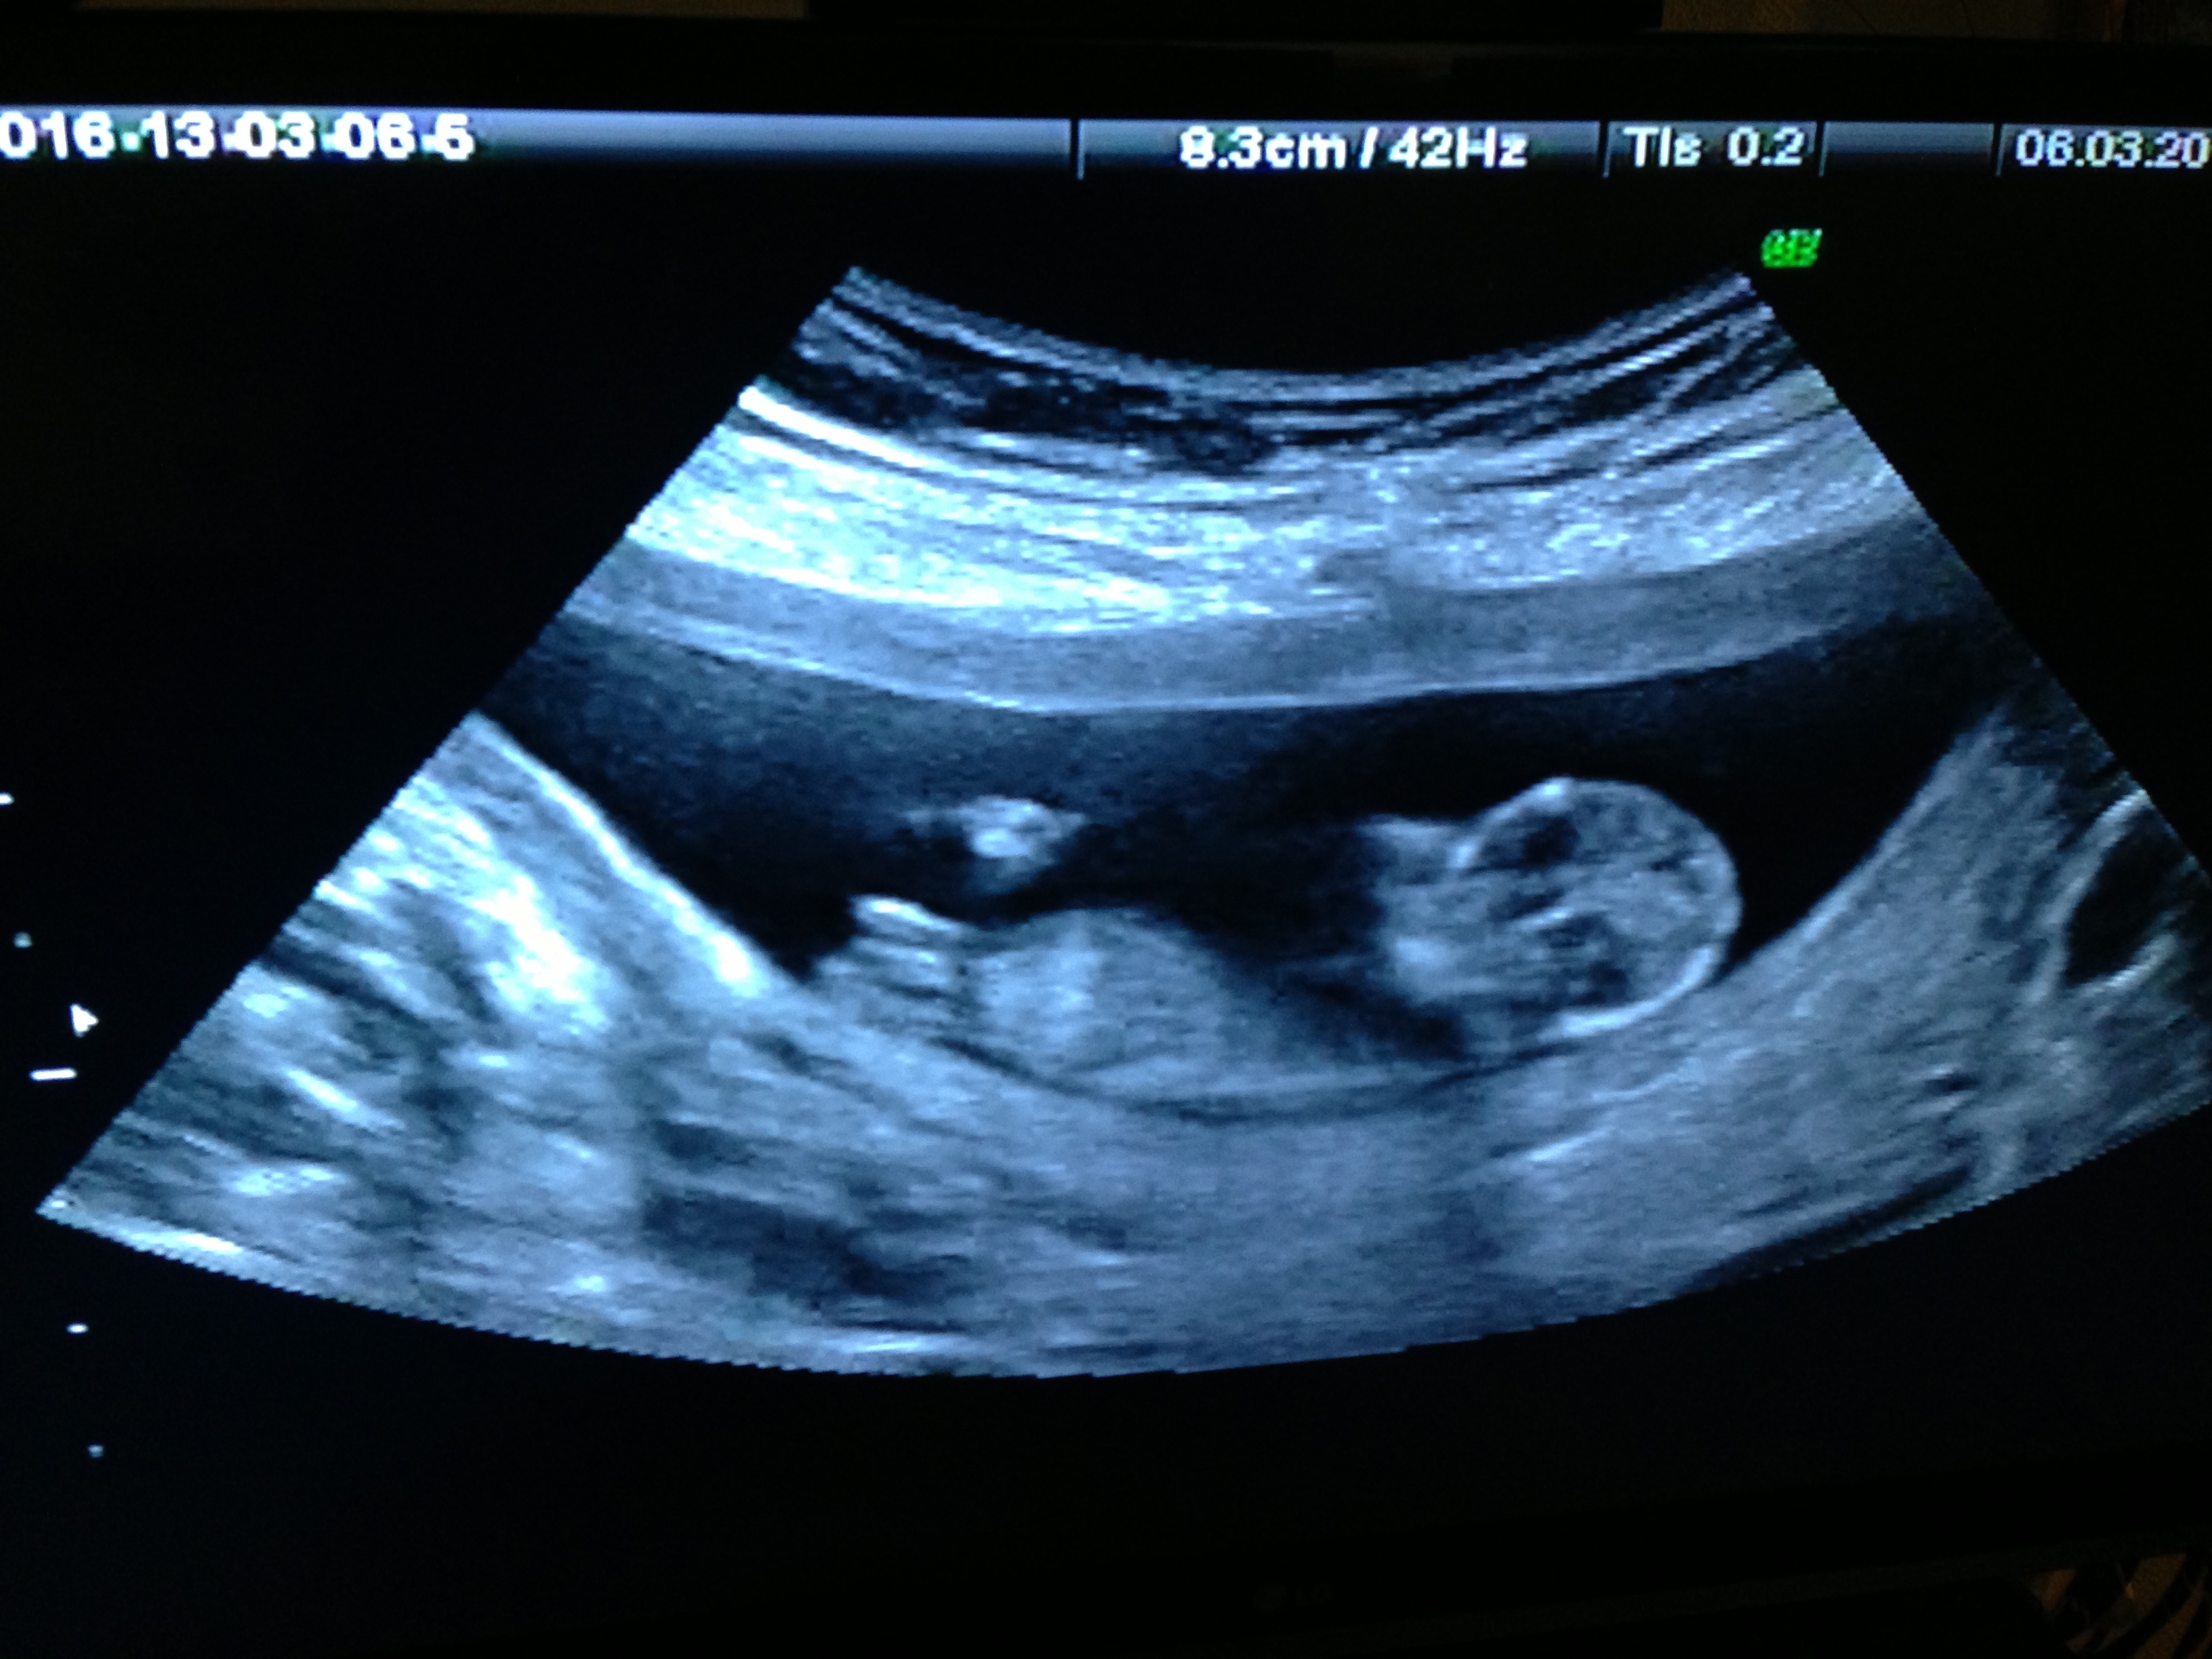

Can you tell me if my second child will be boy or girl???

Do you confirm girl???

Slight pink lean. Watching the video there were a couple times I thought I saw a boy bump on the nub but baby was such a wiggler that I'm not sure.

Girl